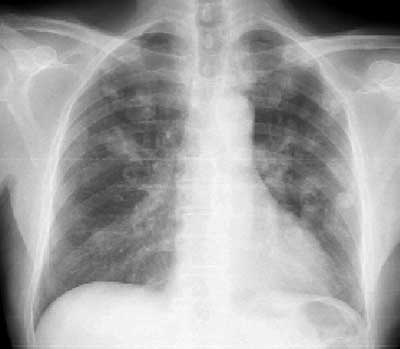

Рис. 1. Цифровая рентгенография легких на аппарате "Пульмоскан-760" (НПП "Адани", Беларусь). Количество, величина, форма, интенсивность, структура и контуры патологических образований в легких хорошо определяются.